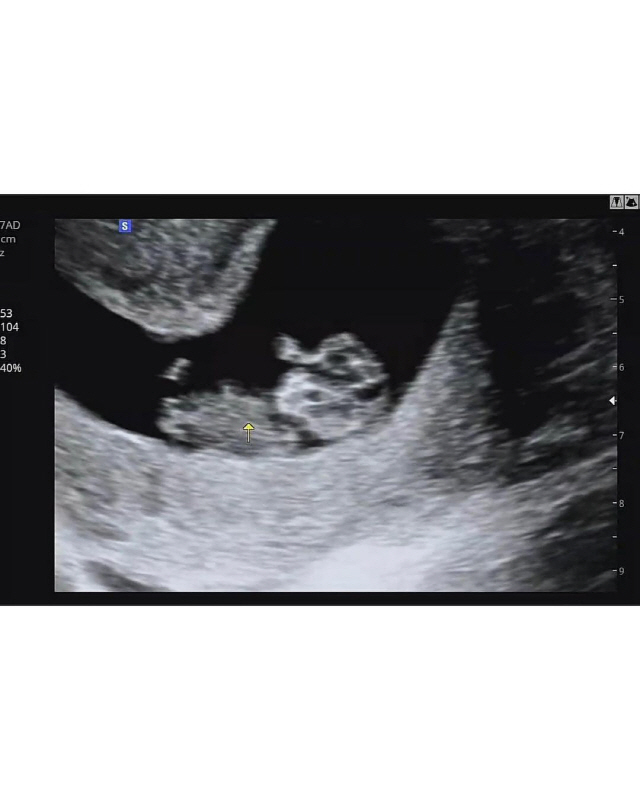

최희는 지난 6일 둘째 임신 소식을 알렸다. 최희는 둘째의 초음파 사진을 공개하며 "둘째 고민이 정말 많았었는데, 최근 건강상 이슈도 있었고 또 제가 두 아이에게 좋은 엄마가 될 수 있을지에 대한 고민도 했다"며 "이 세상에 형제가 있다는 것이 참으로 든든한 일이라는 걸, 복이에게도 둘째에게도 알게 해주고 싶어서, 둘째를 결심하게 되었다. 너무 터울지지 않게 키우고 싶었는데 복이랑은 세 살 차이가 되겠네요"라고 밝혔다.